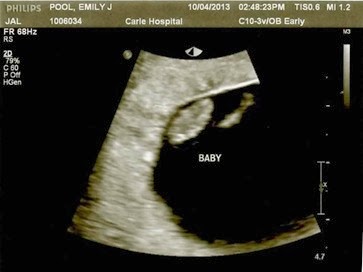

We’re having a blob! Haha. Well, that’s what the picture below looks like anyways. But it’s a blog that has a cute little heartbeat and wicked sense of making their momma sick. Baby Pool #3 is on the way!!

Friday, October 4 – had my first ultrasound and saw a beautiful heartbeat (156 bmp). Also had my first midwife appointment with Carissa, the newest addition to the midwife team.

There was a little debate as I have really LONG cycles and they had me due around May 8. But I knew exactly when I ovulated (well, within a day or so) and the ultrasound confirmed my dating. So May 21st it is. That means that Ellie and her little brother or sister will be about 25 months apart.